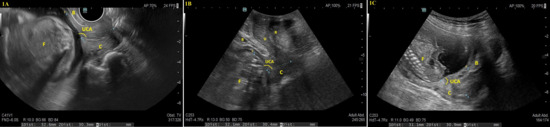

2.4. Data Sources/Measurement